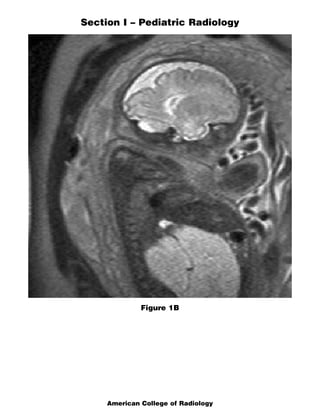

This document contains a multiple choice question and rationales from a pediatric radiology exam. The question shows MRI images of a 22-week fetus and asks for the most likely diagnosis. The rationales eliminate the other answer choices of posterior urethral valves, multicystic dysplastic kidneys, and bilateral ureteropelvic junction obstruction. The correct answer is Autosomal Recessive Polycystic Kidney Disease, as the images show enlarged, fluid-intensity kidneys without urine production, typical of this condition.